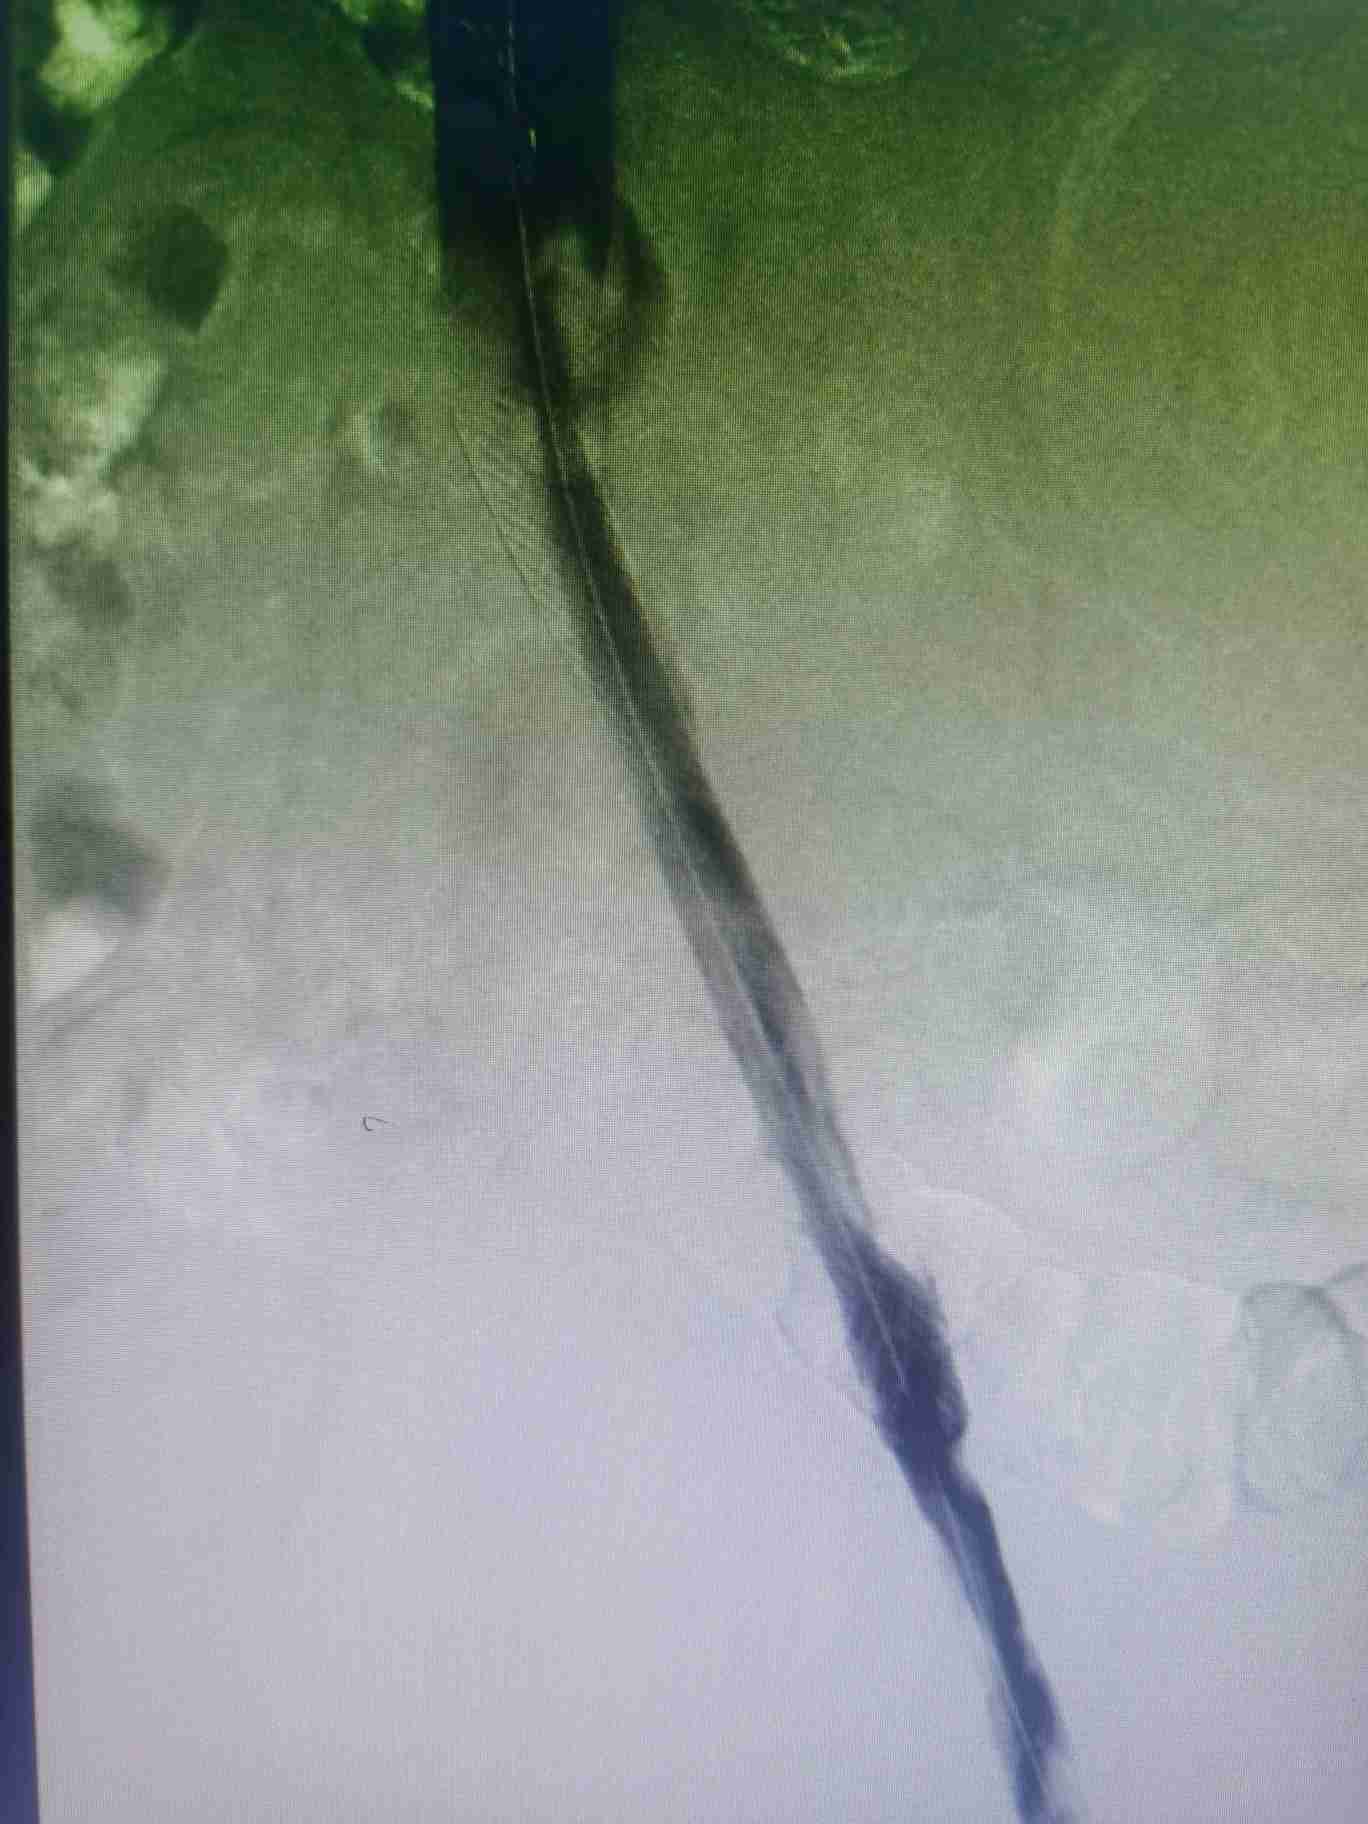

答:首先需要做的就是看医生;然后避免挤压、按摩、揉搓患肢,可用专科垫枕抬高患肢。主要治疗方式为:抗凝、溶栓、外科手术、介入手术等。

答:这个就需要根据患者自身情况制定个性化治疗策略,主要策略为:①保守抗凝治疗:②系统溶栓治疗;③导管接触性溶栓治疗;④机械性血栓清除治疗;⑤必要时球囊扩张和支架植入治疗;⑥急危重症病人需切开取栓治疗等。